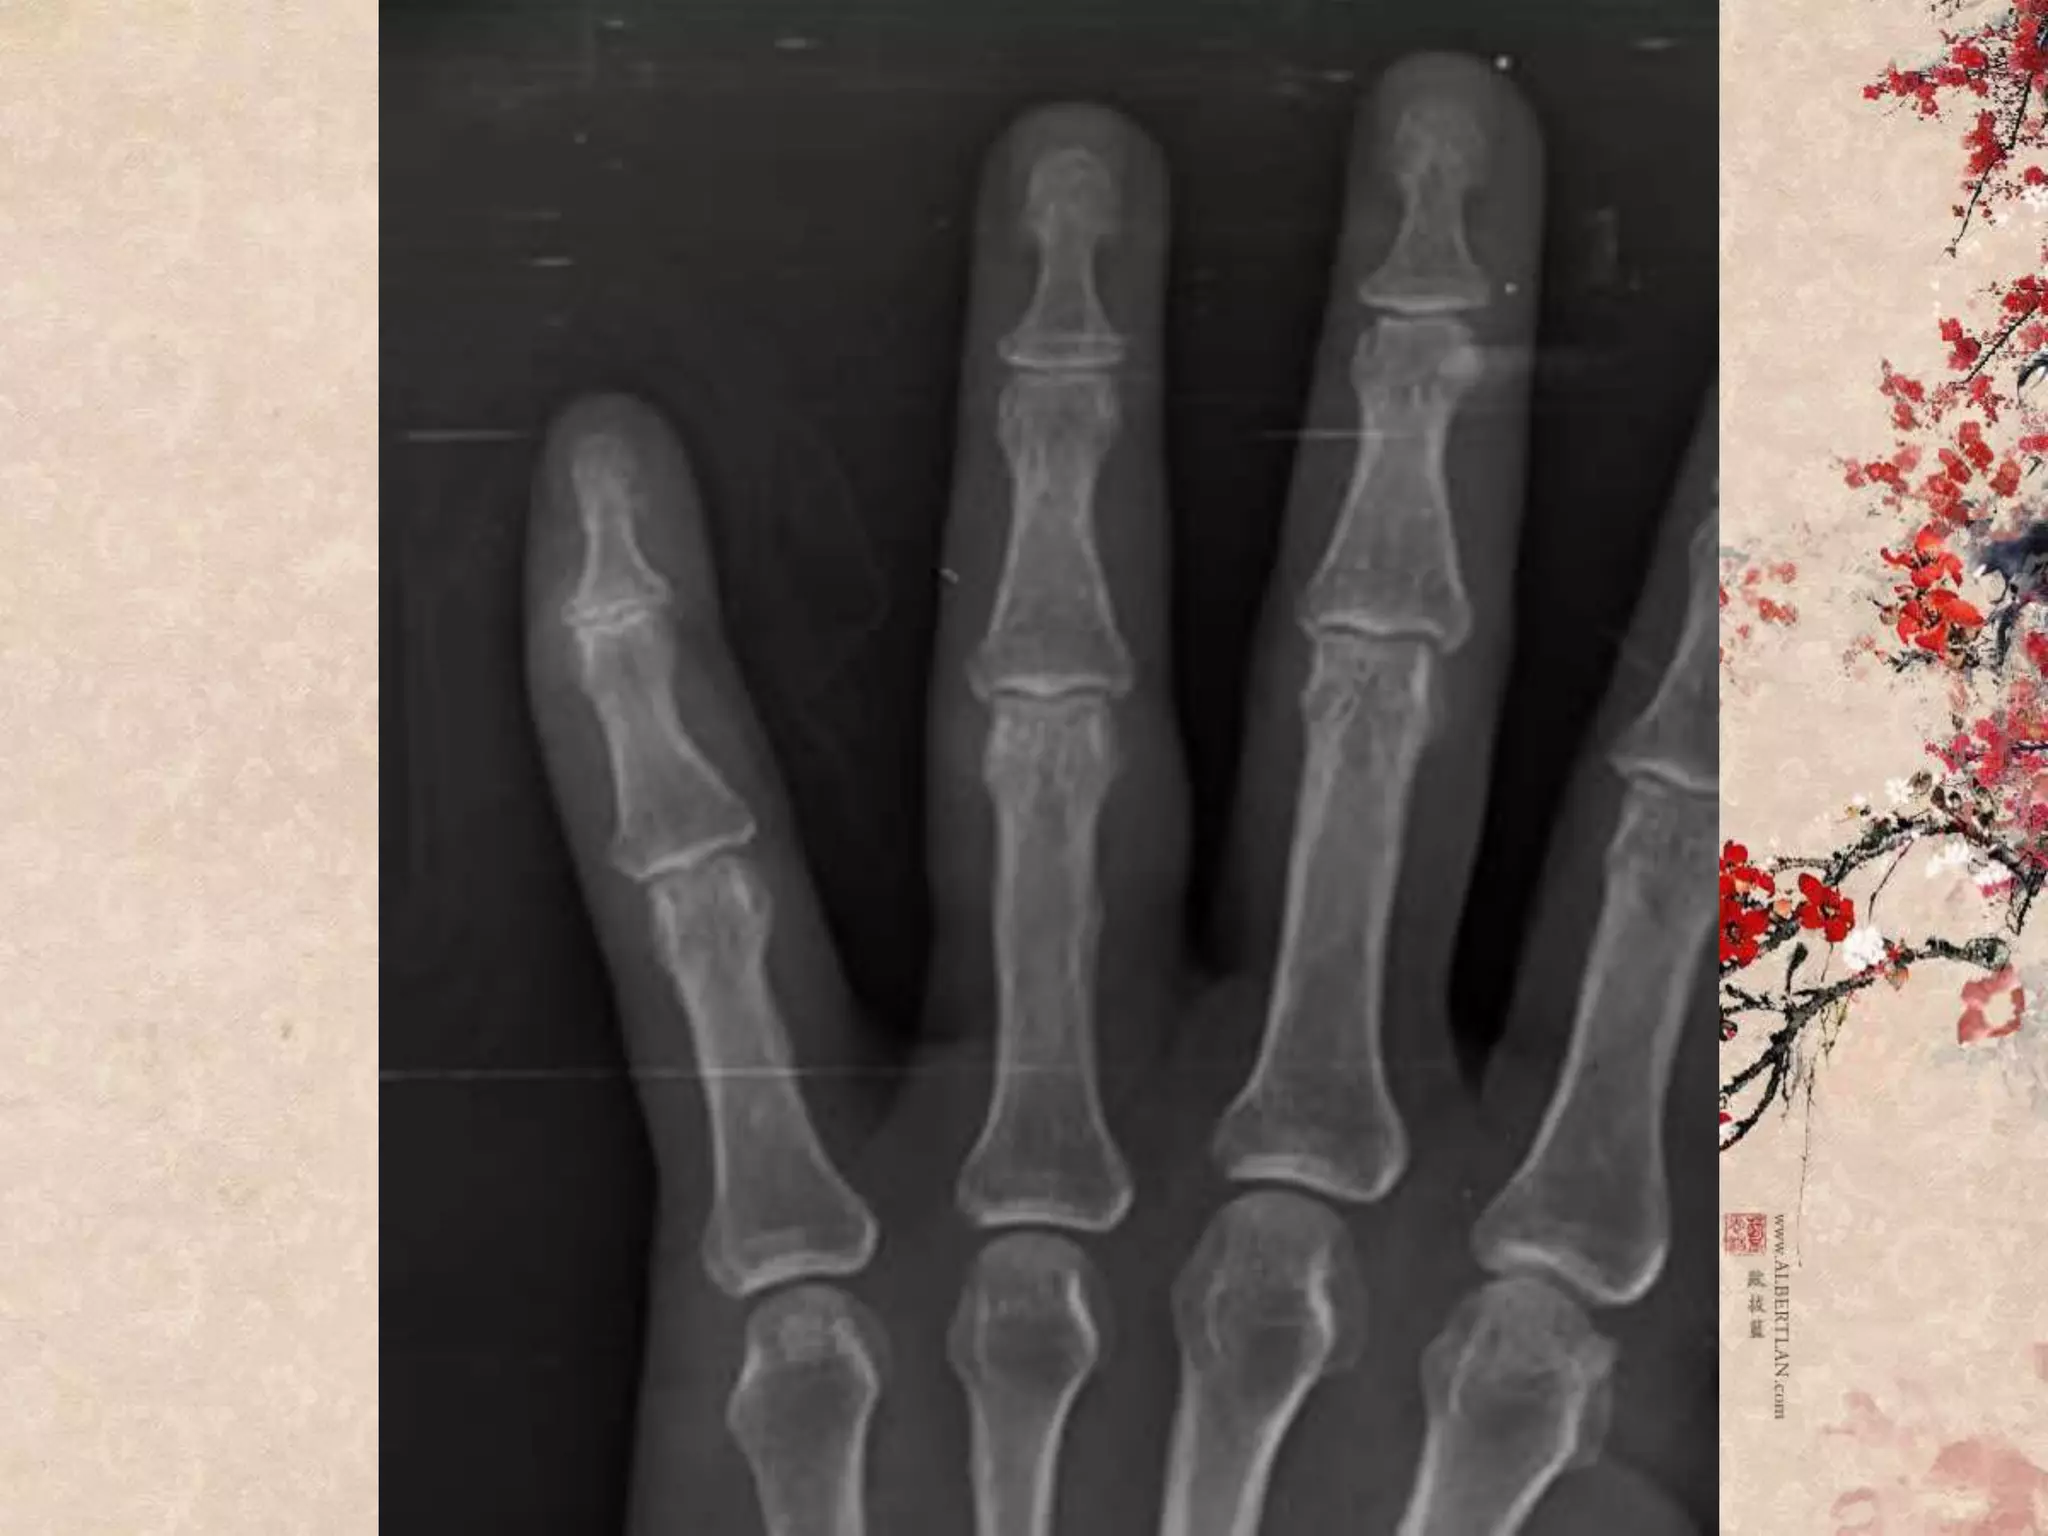

Open Mallet finger

“Extensor tendon injury”

“Mallet finger”

Patient profile หญิงไทย อายุ54 ปี Chief complaint รถจักรยานยนต์ล้มทับนิ้วมือซ้าย 2 ชั่วโมง ก่อนมาโรงพยาบาล

Primary survey A :can talk, no c-spine tenderness B : no dyspnea, RR 20 C : no active external bleeding full pulse, BP 102/80 D : E4V5M6 E : laceration wound 3 cm at Lt. ring finger, deep to bone

Secondary survey A :no drug/food allergy M : no medication P : no underlying disease L : last meal 4 hr E : รถจักรยานยนต์ที่จอดอยู่ ล้มทับนิ้วก้อยมือซ้าย มีแผลเปิด ปวดมาก ขยับนิ้วก้อยได้ ไม่ชาปลายนิ้ว มีเลือดออกซึมๆ เหตุเกิด 2 hr